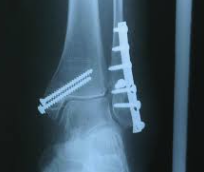

大動物踵骨の骨折 牛、馬の踵骨隆起の骨折はかなり稀です。おこるとすれば、馬では他の馬に蹴られるか、固いものを蹴る、または肢を深い穴につっこむことが原因です。単純または複雑骨折が生じ、後者では、しばしば腐骨が形成されます。骨折脱臼がおこること...